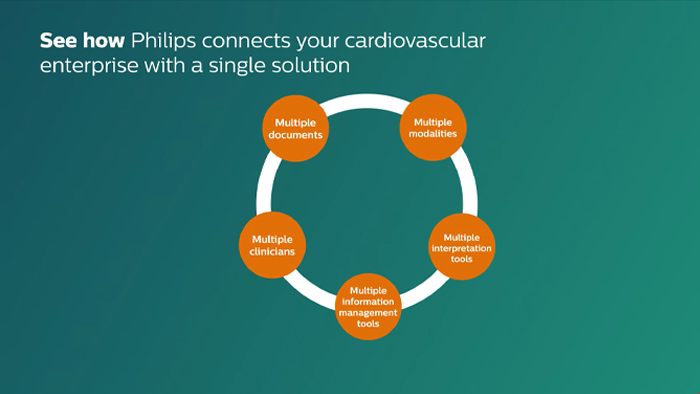

Cardiovascular Workspace

Cardiovascular Workspace is designed to help streamline workflow and improve operational performance throughout the cardiovascular care continuum.